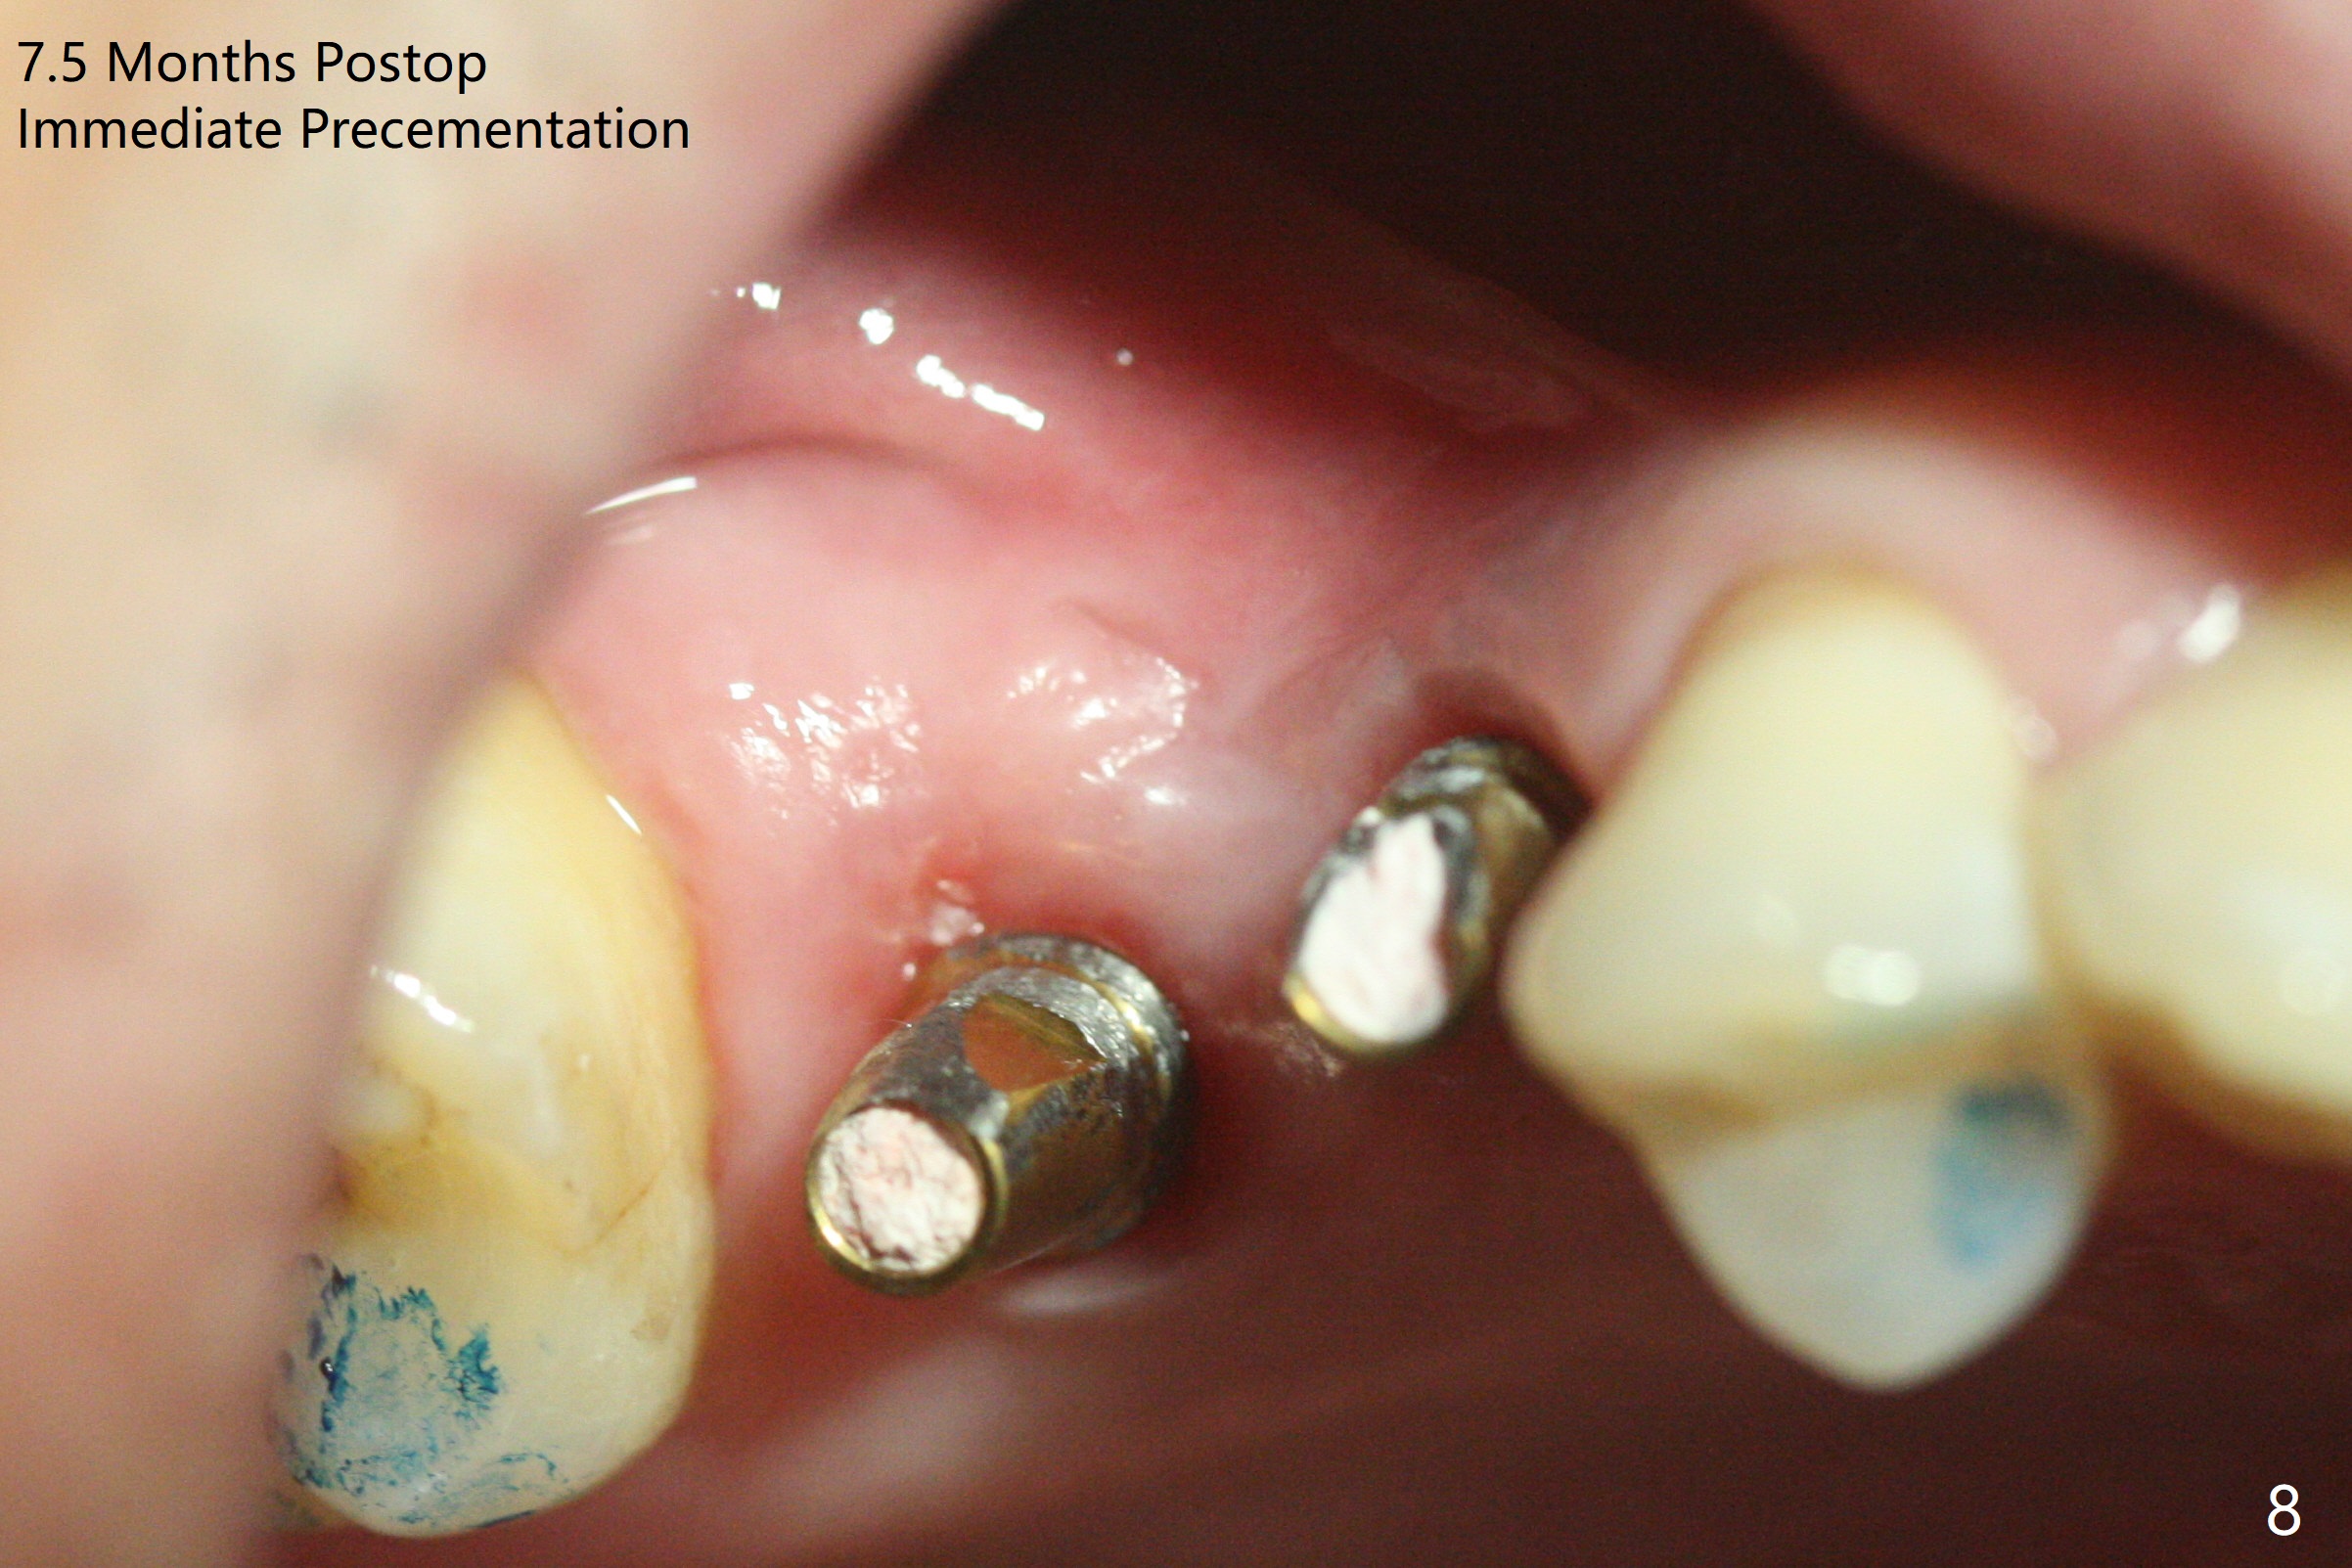

When the tooth #3 with severe buccal gingival recession is extracted and implants are placed at #3 and 4 with guide, sticky bone in 2 large pieces is packed between these implants with a previously large defect in a seemingly secure manner (Fig.1 *). Use of a longer implant at #3 (11.5 mm vs. 10 mm) will reduce the chance of abutment screw loosening in the future. With 2 pieces of PRF membrane coverage, an immediate provisional is fabricated for graft retention (Fig.2,3 P). To stabilize a buccal flap (Fig.2 *, used to be buccal furca gingiva), periodontal dressing is applied later. The buccal socket heals 12 days postop (Fig.4). Apparently new bone forms between the implants 4 months postop (Fig.5). The abutment at #3 may not be completely seated. In fact it is loose, probably related to buccal gingival and gingival cuff erythema 6.5 months postop (Fig.6). Large healing abutments are placed to form the interdental (interimplant) papilla without effect (*). Provisional crowns will be fabricated for the papilla formation. When cemented abutments are placed (Fig.7), papilla formation by manipulation of provisional crowns seems unlikely. Impression is taken. Although there is no implant thread exposure, the buccal plate is concave 7.5 months postop (Fig.8). With special crown design, food impaction should be minimal post cementation (Fig.9,10). There is no bone loss 5.5 months post cementation (Fig.11), while the soft tissue is healthy (data not shown).